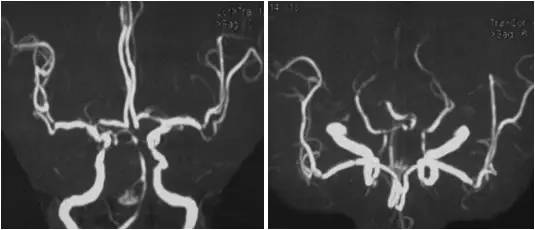

MRA:基底动脉中远段重度狭窄,右后交通动脉开放,左胚胎型大脑后动脉,双颈内动脉颅内段及双大脑中动脉多发轻-中度狭窄(图2)。

图2